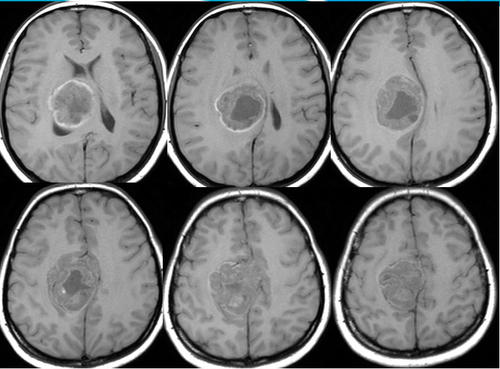

质子治疗室管膜瘤效果好吗?通过减少进入前颅结构(如耳蜗、脑下垂体和颞叶)的放射剂量,质子可以降低室管膜瘤患者的晚期毒性风险。室管膜瘤患者在接受放射治疗时通常很年轻,诊断时的平均年龄为5-6岁。麦克唐纳等人的一项研究强调了质子治疗的剂量学益处,该研究比较了17例后颅底室管膜瘤儿童的质子治疗和调强放疗(IMRT)计划的剂量分布。通过质子疗法可以观察到对整个大脑和颞叶的辐射剂量减少。尽管调强放疗的耳蜗剂量也很低(平均剂量3 Gy),但质子对耳蜗的放射剂量基本上没有受到任何影响。

MacDonald等人也发表了大量的质子治疗室管膜瘤的临床系列,包括2000年至2011年在MGH治疗的70例局限性疾病的儿童。中位年龄为38个月,大多数患者有幕下疾病(73%)、经典组织学(53%)和全切除(GTR)(66%)。质子的中位剂量为55.8 Gy(相对生物学效应[RBE]),57%的患者接受的剂量高于54 Gy(RBE)。在46个月的中位随访中,3年的局部控制(LC)、无进展生存期(PFS)和总生存期(OS)分别为83%、76%和95%。甲状腺功能减退的患者占1/32(3%),生长激素缺乏的患者占2/25(8%)。生长激素缺乏的比率可能与脑积水混淆,在治疗前有54%的患者存在脑积水。耳蜗中位剂量为7 Gy(RBE),但由于延伸至四脑室外侧孔,需要覆盖至或进入内耳道,剂量范围为0~54 Gy(RBE)。有2/23(9%)可评估的患者因辐射而导致听力损失,两者均因疾病提前扩展而接受了几乎全剂量的耳蜗治疗。队列中无脑干坏死病例。

Ares等在文献的基础上发表了在Paul Scherer研究所用质子治疗50例颅内室管膜瘤的结果。中位年龄为31个月,中位辐射剂量为59.4 Gy(RBE),72%患有幕下疾病,66%接受全切除(GTR)。5年LC率和OS率分别为78%和84%,有残留疾病者和无残留疾病者的LC率分别为77%和91%。治疗后中枢性甲状腺功能减退和生长激素缺乏的发生率均为6%。单侧听力丧失2例(4%)。一名患者死于致命的脑干坏死;该患者较初接受GTR和化疗治疗,复发后需要在放疗之前进行二次手术。二次手术因脑干梗塞和脑膜炎而复杂化。

Sato等人发表了他们对德克萨斯州儿童医院使用光子(38例)或质子(41例)放疗和MDACC治疗的79例室管膜瘤患者的回顾性分析。3年的PFS率在光子组为60%,在质子组为82%(P=0.031),两组之间的LC率没有差异(两组为86%)。全部失效都发生在高剂量区。接受质子治疗的患者更年轻(中位年龄,2.5岁对5.7岁;P=0.001),中位随访时间更短(2.6年比4.9年;P<0.0001)。质子组的GTR频率高于调强放疗IMRT组(93%比76%);P=0.043)。6例患者(光子组3例,质子组3例)出现症状并经影像学诊断为放射性坏死。

较近,Indelicato等人发表了179例非转移性II/III级室管膜瘤儿童使用质子治疗的结果。在平均3.2年的随访中,临床结果与3年LC和OS分别为85%和90%的光子序列相当。3年的PFS为76%。与其他系列相似,多因素分析发现次全切除与下段LC(67%比88%,P≤0.01)和PFS(59%比79%,P&<0.05)相关。有趣的是,男性也与较低的PFS(67%vs 87%,P<0.05)和OS(84%vs.99%,P<0.01)相关。10例患者出现症状性脑干毒性,经过精算的3年不良事件通用术语标准(CTCAE),2级+脑干毒性率为5.5%(95%CI:2.9-10.2),其中1例出现5级毒性。